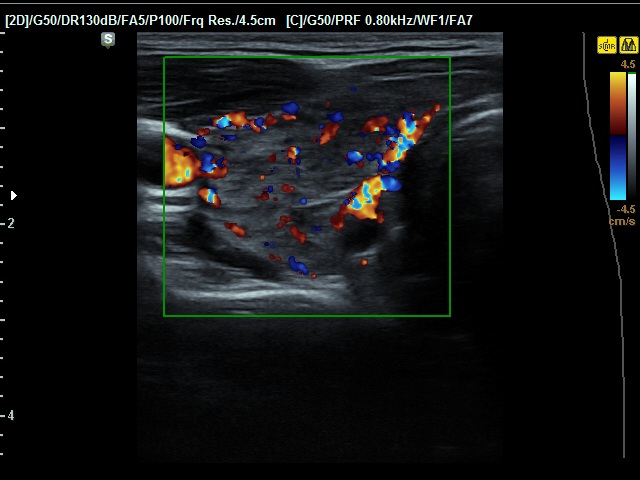

Consecutive patients with the final diagnosis of Hashimoto's thyroiditis - case 50 (329) (ultrasonographic picture 3)

Right lobe, transverse scan, color Doppler mode. The vascularization is a bit increased.